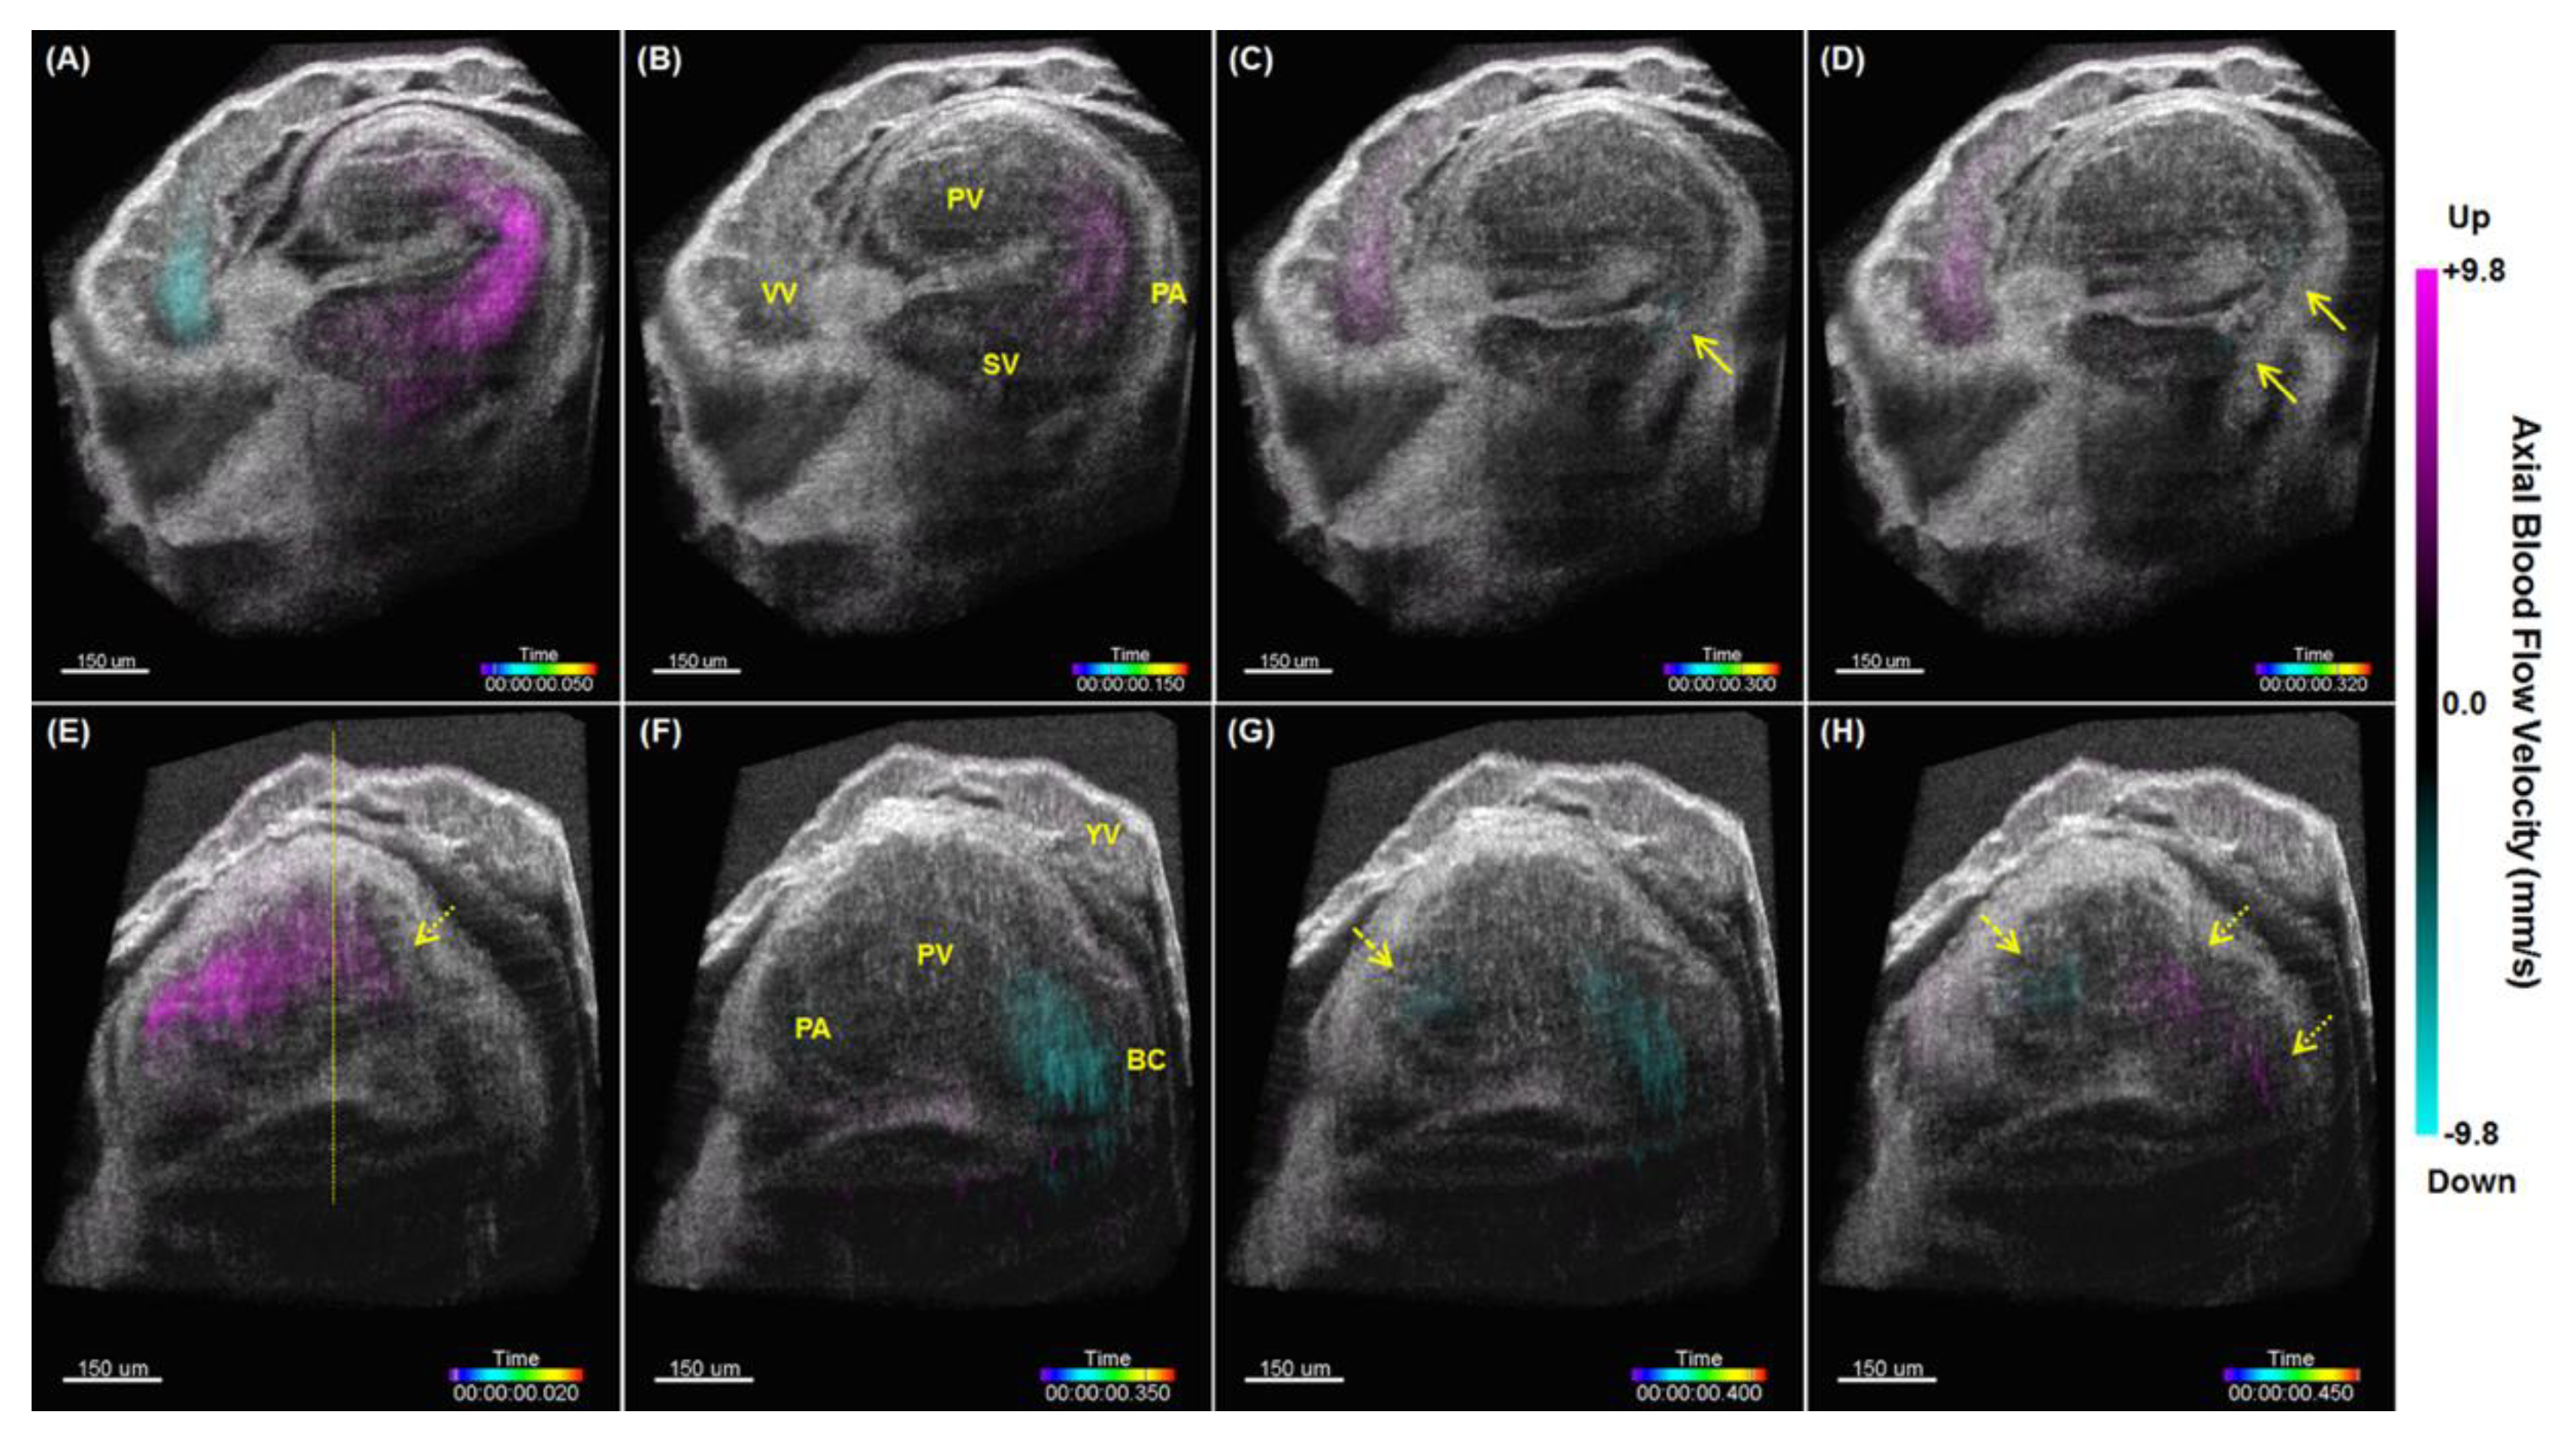

5. Hemodynamic Imaging with Doppler OCT

- Wang, S.; Lakomy, D.S.; Garcia, M.D.; Lopez, A.L.; Larin, K.V.; Larina, I.V. Four-dimensional live imaging of hemodynamics in mammalian embryonic heart with Doppler optical coherence tomography. J. Biophotonics 2016, 9, 837–847. [Google Scholar] [CrossRef] [Green Version]

- Wang, S.; Larina, I.V. Live mechanistic assessment of localized cardiac pumping in mammalian tubular embryonic heart. J. Biomed. Opt. 2020, 25, 086001. [Google Scholar] [CrossRef]